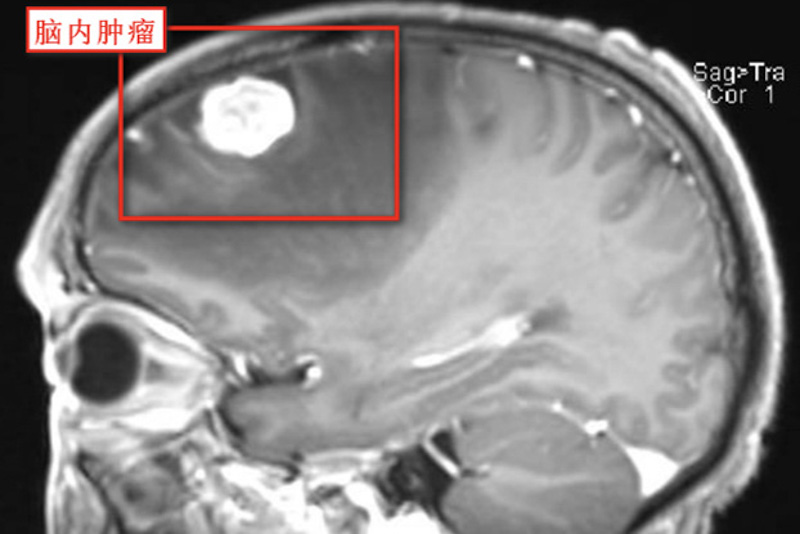

54歲的孟先生(化名)近期逐漸出現(xiàn)了頭痛、言語混亂、答非所問等癥狀,家人發(fā)現(xiàn)后立即將其送入柳州市人民醫(yī)院神經(jīng)外科,經(jīng)磁共振檢查提示左側(cè)額葉有一腫瘤,周邊水腫明顯,毗鄰語言區(qū),必須盡快進行手術(shù)治療。

膠質(zhì)瘤是起源于腦神經(jīng)膠質(zhì)細胞的腫瘤,是最常見的原發(fā)性顱內(nèi)腫瘤,近些年來,原發(fā)性惡性腦腫瘤的發(fā)病率逐年遞增,膠質(zhì)瘤約占其中的27%。膠質(zhì)瘤治療以手術(shù)切除腫瘤為主,結(jié)合放療、化療等綜合治療方法,手術(shù)目的是保護正常腦組織、功能情況下盡最大程度安全切除腫瘤,由于膠質(zhì)瘤無包膜,無明顯邊界,與正常腦神經(jīng)組織“融為一體”,手術(shù)難點是清晰顯示腫瘤界線,判斷是否有腫瘤殘留,而有了術(shù)中腫瘤熒光技術(shù),以上問題均可迎刃而解。